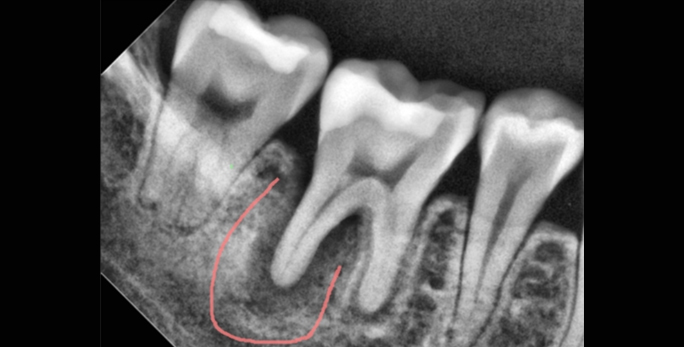

• 타원신경치료 실패 후 발치평가 받은 환자 치근단 절제술로 발치하지 않고 부러진 기구 제거 및 치아 보존